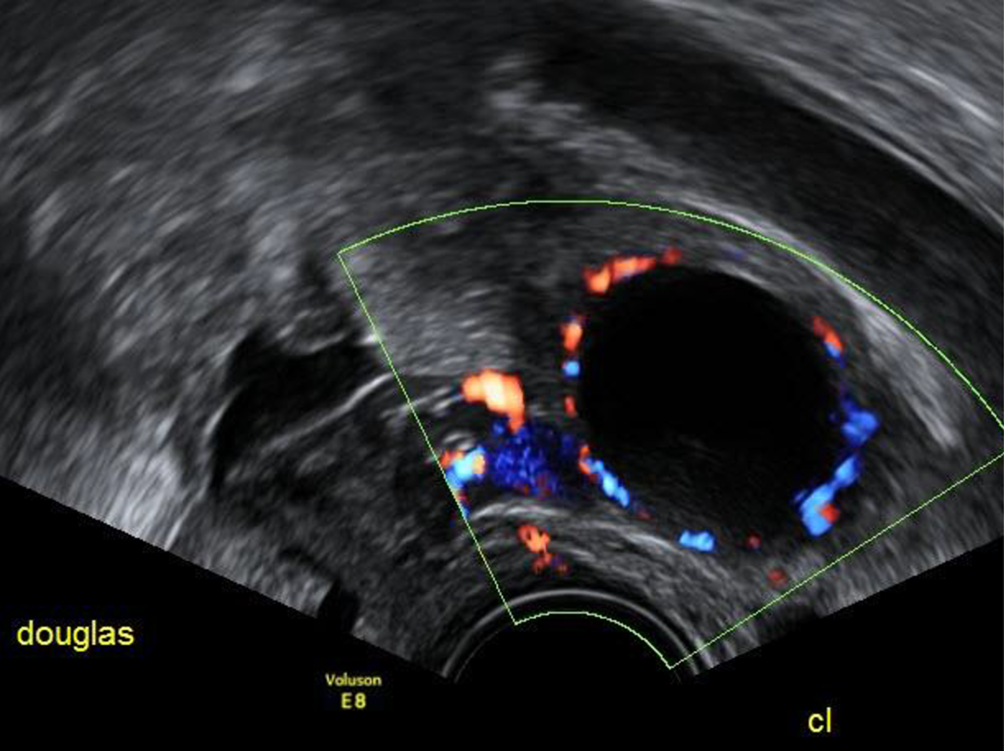

Abb. 3

Dieses Corpus luteum hat eine große „central fluid-filled cavity“ ohne Zeichen von Koageln im Inneren. Dieser Befund wird auch „follicular refilling“ genannt

Abb. 4

In diesem Fall des „follicular refilling“ haben sich Koagel gebildet, die knapp die Hälfte des Flüssigkeitsraums ausfüllen. Sie sind nicht vaskularisiert

Sehr hilfreich ist der Farbdoppler bei der Feststellung eines Corpus luteum – die für die endokrine Aktivität des Organs nötige periphere Vaskularisation zeigt sich in einer meist kreisrunden, 1–2 cm großen charakteristischen Struktur im Ovar – im Ultraschalljargon, seit es den Farbdoppler gibt, als „ring of fire“ bekannt. Diese Vaskularisation nimmt rund 10 Tage nach der Ovulation ab, mit Beginn der Monatsblutung ist sie kaum mehr vorhanden. Solide Strukturen im Inneren der Flüssigkeit kann man nur dann sicher als Koagel beschreiben, wenn sie im Farbdoppler nicht vaskularisiert sind. Wären die echodensen Strukturen innerhalb der Flüssigkeit in Abb. 4 vaskularisiert, müsste die Verdachtsdiagnose auf ein Muzinkystom oder ein Malignom lauten und der Befund müsste nach den IOTA-Kriterien beurteilt werden [1].